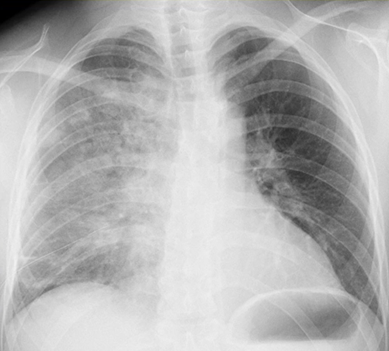

X-pでは浸潤影やすりガラス陰影